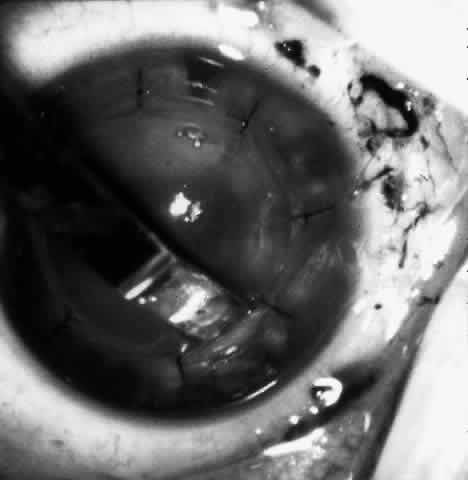

Sixteen to 22 interrupted 10-0 nylon sutures are placed to secure the edge of the lens in the peripheral corneal stroma trough. The first eight sutures are placed with the edge of the lens lying over the circular trephine mark (Fig. 10). As with any corneal transplant surgery, the second suture is the most important in centering the lens. All knots must be tied in such a way that the knots may be buried easily. At the same time, the sutures must not be tightened so tightly that compression occurs with the lens. My personal preference is for a 2-1-1 surgeon's knot. Care should be taken to prevent the lens from being sewn eccentrically into the bed, to prevent astigmatism. After the first eight sutures are placed, the edge of the lens is tucked into the stromal bed all around (Fig. 11) and the remaining 8 to 14 sutures are placed to fasten the lens securely in place (Fig. 12). The sutures are rotated so that the knots are buried in the recipient cornea. This allows the surgeon to remove the sutures at a subsequent examination under anesthesia (EUA) by means of traction directed peripherally without dehiscence of the wound.

Fig. 12. The remaining eight sutures are placed with the lenticule edges tucked.